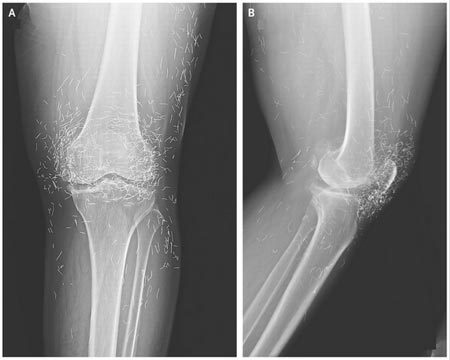

| Phim chụp X-quang cho thấy, hàng trăm chiếc kim bằng vàng cố ý bị bỏ lại bên trong mô đầu gối của nữ bệnh nhân cao tuổi. Ảnh: New England Journal of Medicine |

Khi các bác sĩ kiểm tra phim chụp X-quang hai đầu gối của một cụ bà đang bị đau khớp nghiêm trọng, họ đã phát hiện một "mỏ" vàng, thực chất là hàng trăm chiếc kim châm cứu tí hon bằng vàng, bị bỏ lại trong mô của bà.